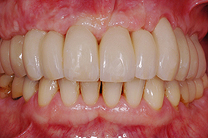

Gesamtrekonstruktionen

Fehlen in einem Kiefer alle Zähne oder sind die meisten Zähne in einem schlechten, nicht erhaltungswürdigen Zustand, ist es sinnvoll eine Gesamtrekonstruktion anzufertigen. Diese kann sowohl dental als auch implantat-getragen sein. Die Gesamtrekonstruktionen sind zeitlich wie finanziell aufwendig, bestechen aber durch ihre Ästhetik und die Langlebigkeit. Der Vorteil ist, dass viele kleine Arbeiten und Reparaturen in den nächsten Jahren wegfallen werden.